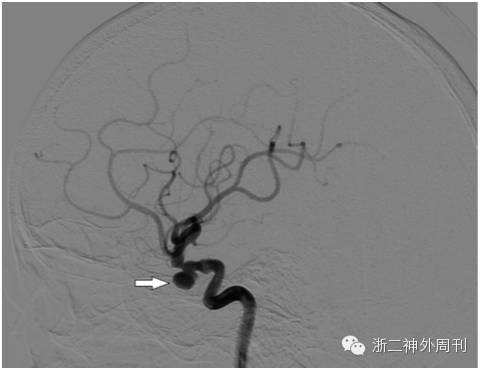

基于上述所见,考虑异物可能伤及颈内动脉,行急诊DSA检查,显示右侧颈内动脉受压变形,动脉壁不光整,未见造影剂外渗(图3)。在导管室临时球囊闭塞颈内动脉下,小心行异物拔除术,撤除临时闭塞球囊后,未见窦道活动性出血。取出的异物为枯竹,测量总长度约为7cm左右,与术前测量长度接近(图4)。将手术情况及还有异物残留可能等告知家属。

图3. DSA检查,显示右侧颈内动脉受压变形,动脉壁不光整。